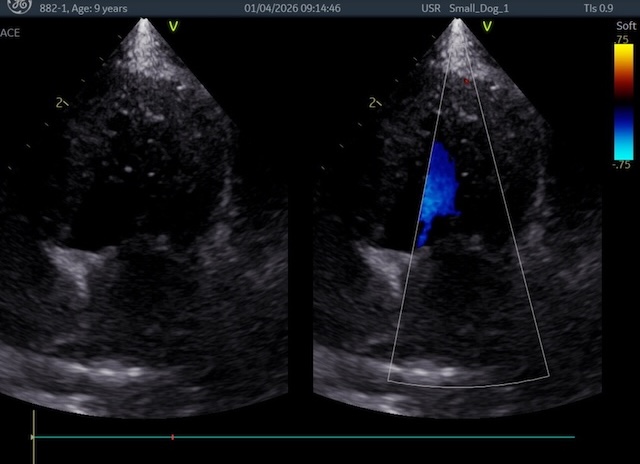

術後は、逆流も消失し、左心房、左心室がかなり小さくなってくれました。